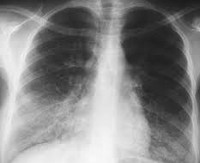

J17.2 Пневмония при микозах